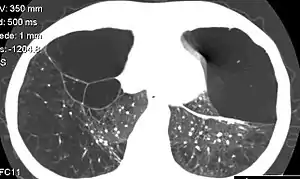

| CT scan of the lung showing bullae in the lower lung lobes of a subject with type alpha-1-antitrypsin deficiency. There is also increased lung density in areas with compression of lung tissue by the bullae. | |

- A bulla has a wall thickness of less than 1 mm.[2] By radiology definition, is has a total size of greater than 1 cm.[3] By pathology definition, it originates in the lung parenchyma (rather than in the pleurae).[4]